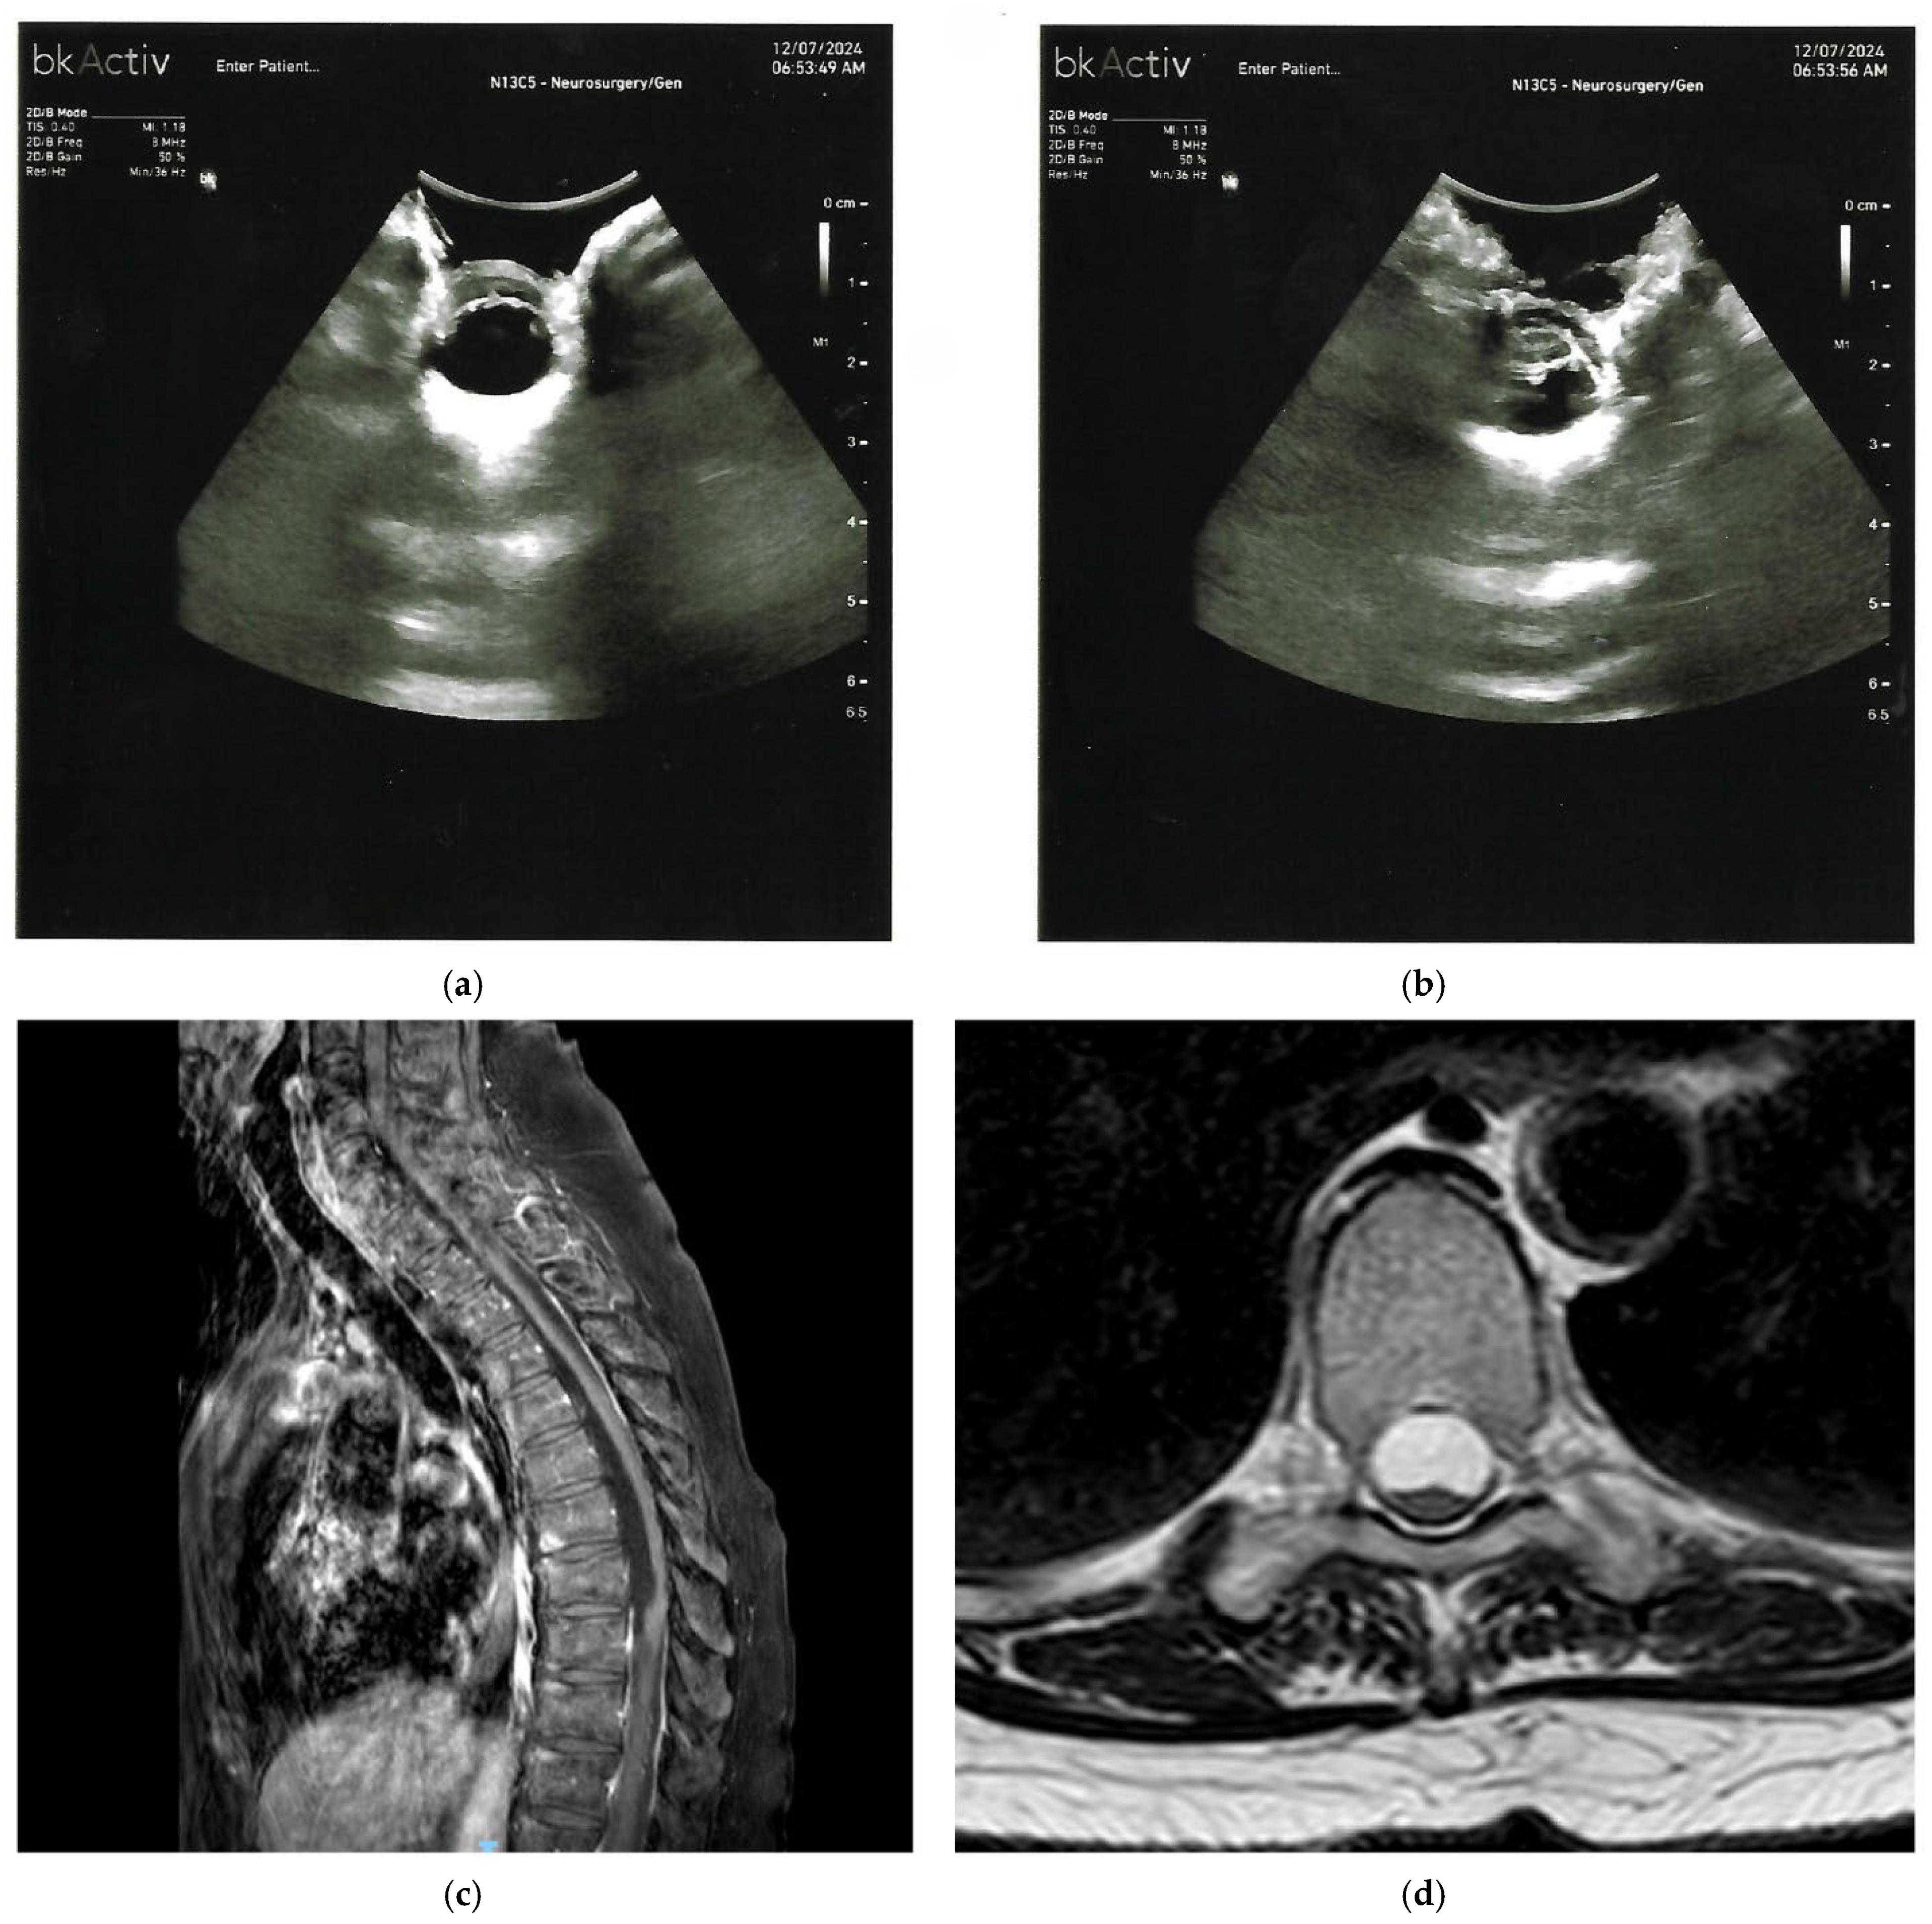

| Neuroenteric or Respiratory Cysts | Well circumscribed, cerebrospinal fluid-like signal on T2; no enhancing solid component; focal cord compression. | Anechoic or hypoechoic cavity with well-defined margins, echogenic lining, occasional septations; eccentric cord displacement. |